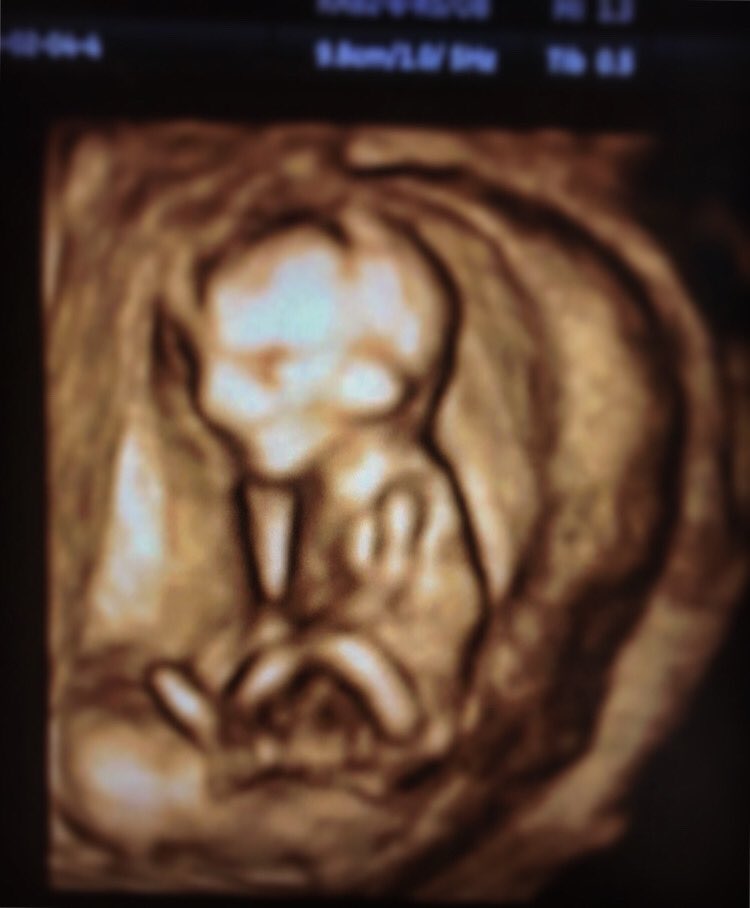

Kadın hastalıkları ve doğum bulunduğu hastane. Oskar öğüten in görev yaptığı anlaşmalı özel hastanelerimizde ekim 2019 itibariyle a life hospital sgk anlaşması ve sigorta şirketlerimizin sağlık sigortası alternatiflerinden yararlanabilirisiniz. He s at the eryaman hospital dr hussein şenyurt on tunus behind tunali it cost about 220 tl for an obstetric appointment. İnfertilite ve tüp bebek üreme i̇nfertilite cerrahi pelvik muayene ve pap smear fallopi tüpü çıkarılması histerektomi doppler ultrason alanlarında hizmet veriyor ve tüp bebek gebe kalamama suda doğum ay başı kanaması azlığı hipogonadizm.